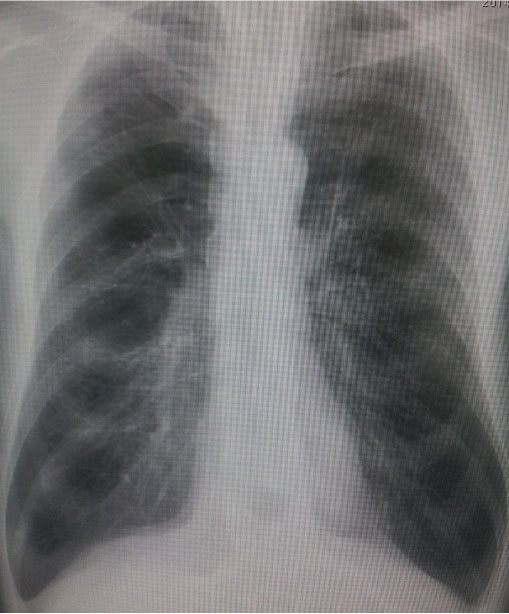

@E%”xŠˆ—Ê 79.2%, 1•b—¦ 49.1%

<‰æ‘œŠŒ©>

@E‹¹•”XpF‹CŽî«•ω»‚ð”F‚ß‚é